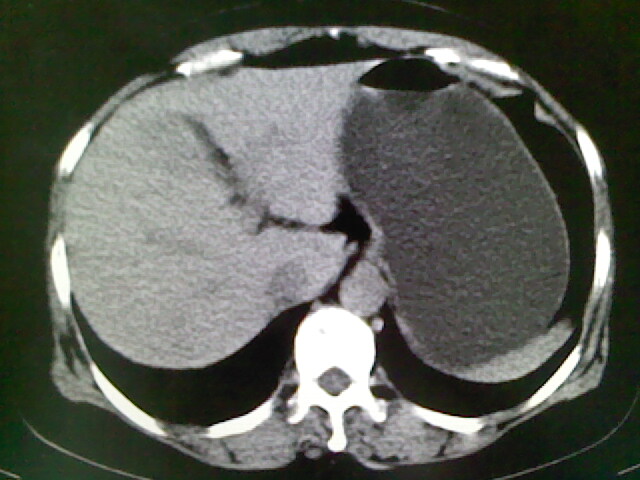

以下是引用卜一在2009-4-2 13:26:00的发言:[br]胆囊颈部结石伴胆囊炎!另:建议增强,待除外肝内占位及胆囊占位!

以下是引用liaoqiang在2009-4-2 16:23:00的发言:[br]胆囊是否切除?胆囊颈区致密影考虑金属夹?结石?肝脏右叶低密度影,考虑增强。